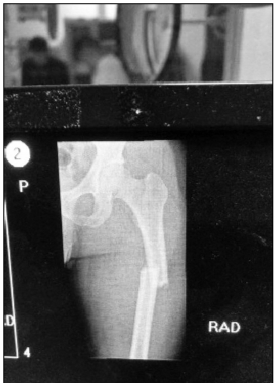

王泽奇大腿骨折的X光片

直到这时,王泽奇才感到左腿一阵剧痛。同事们连忙将他紧急送往医院。经过X光片检查,大家都被惊呆了,他的左腿股骨近端骨折并错位。难以想象他是凭着怎样的毅力,坚持完成了抓捕任务。